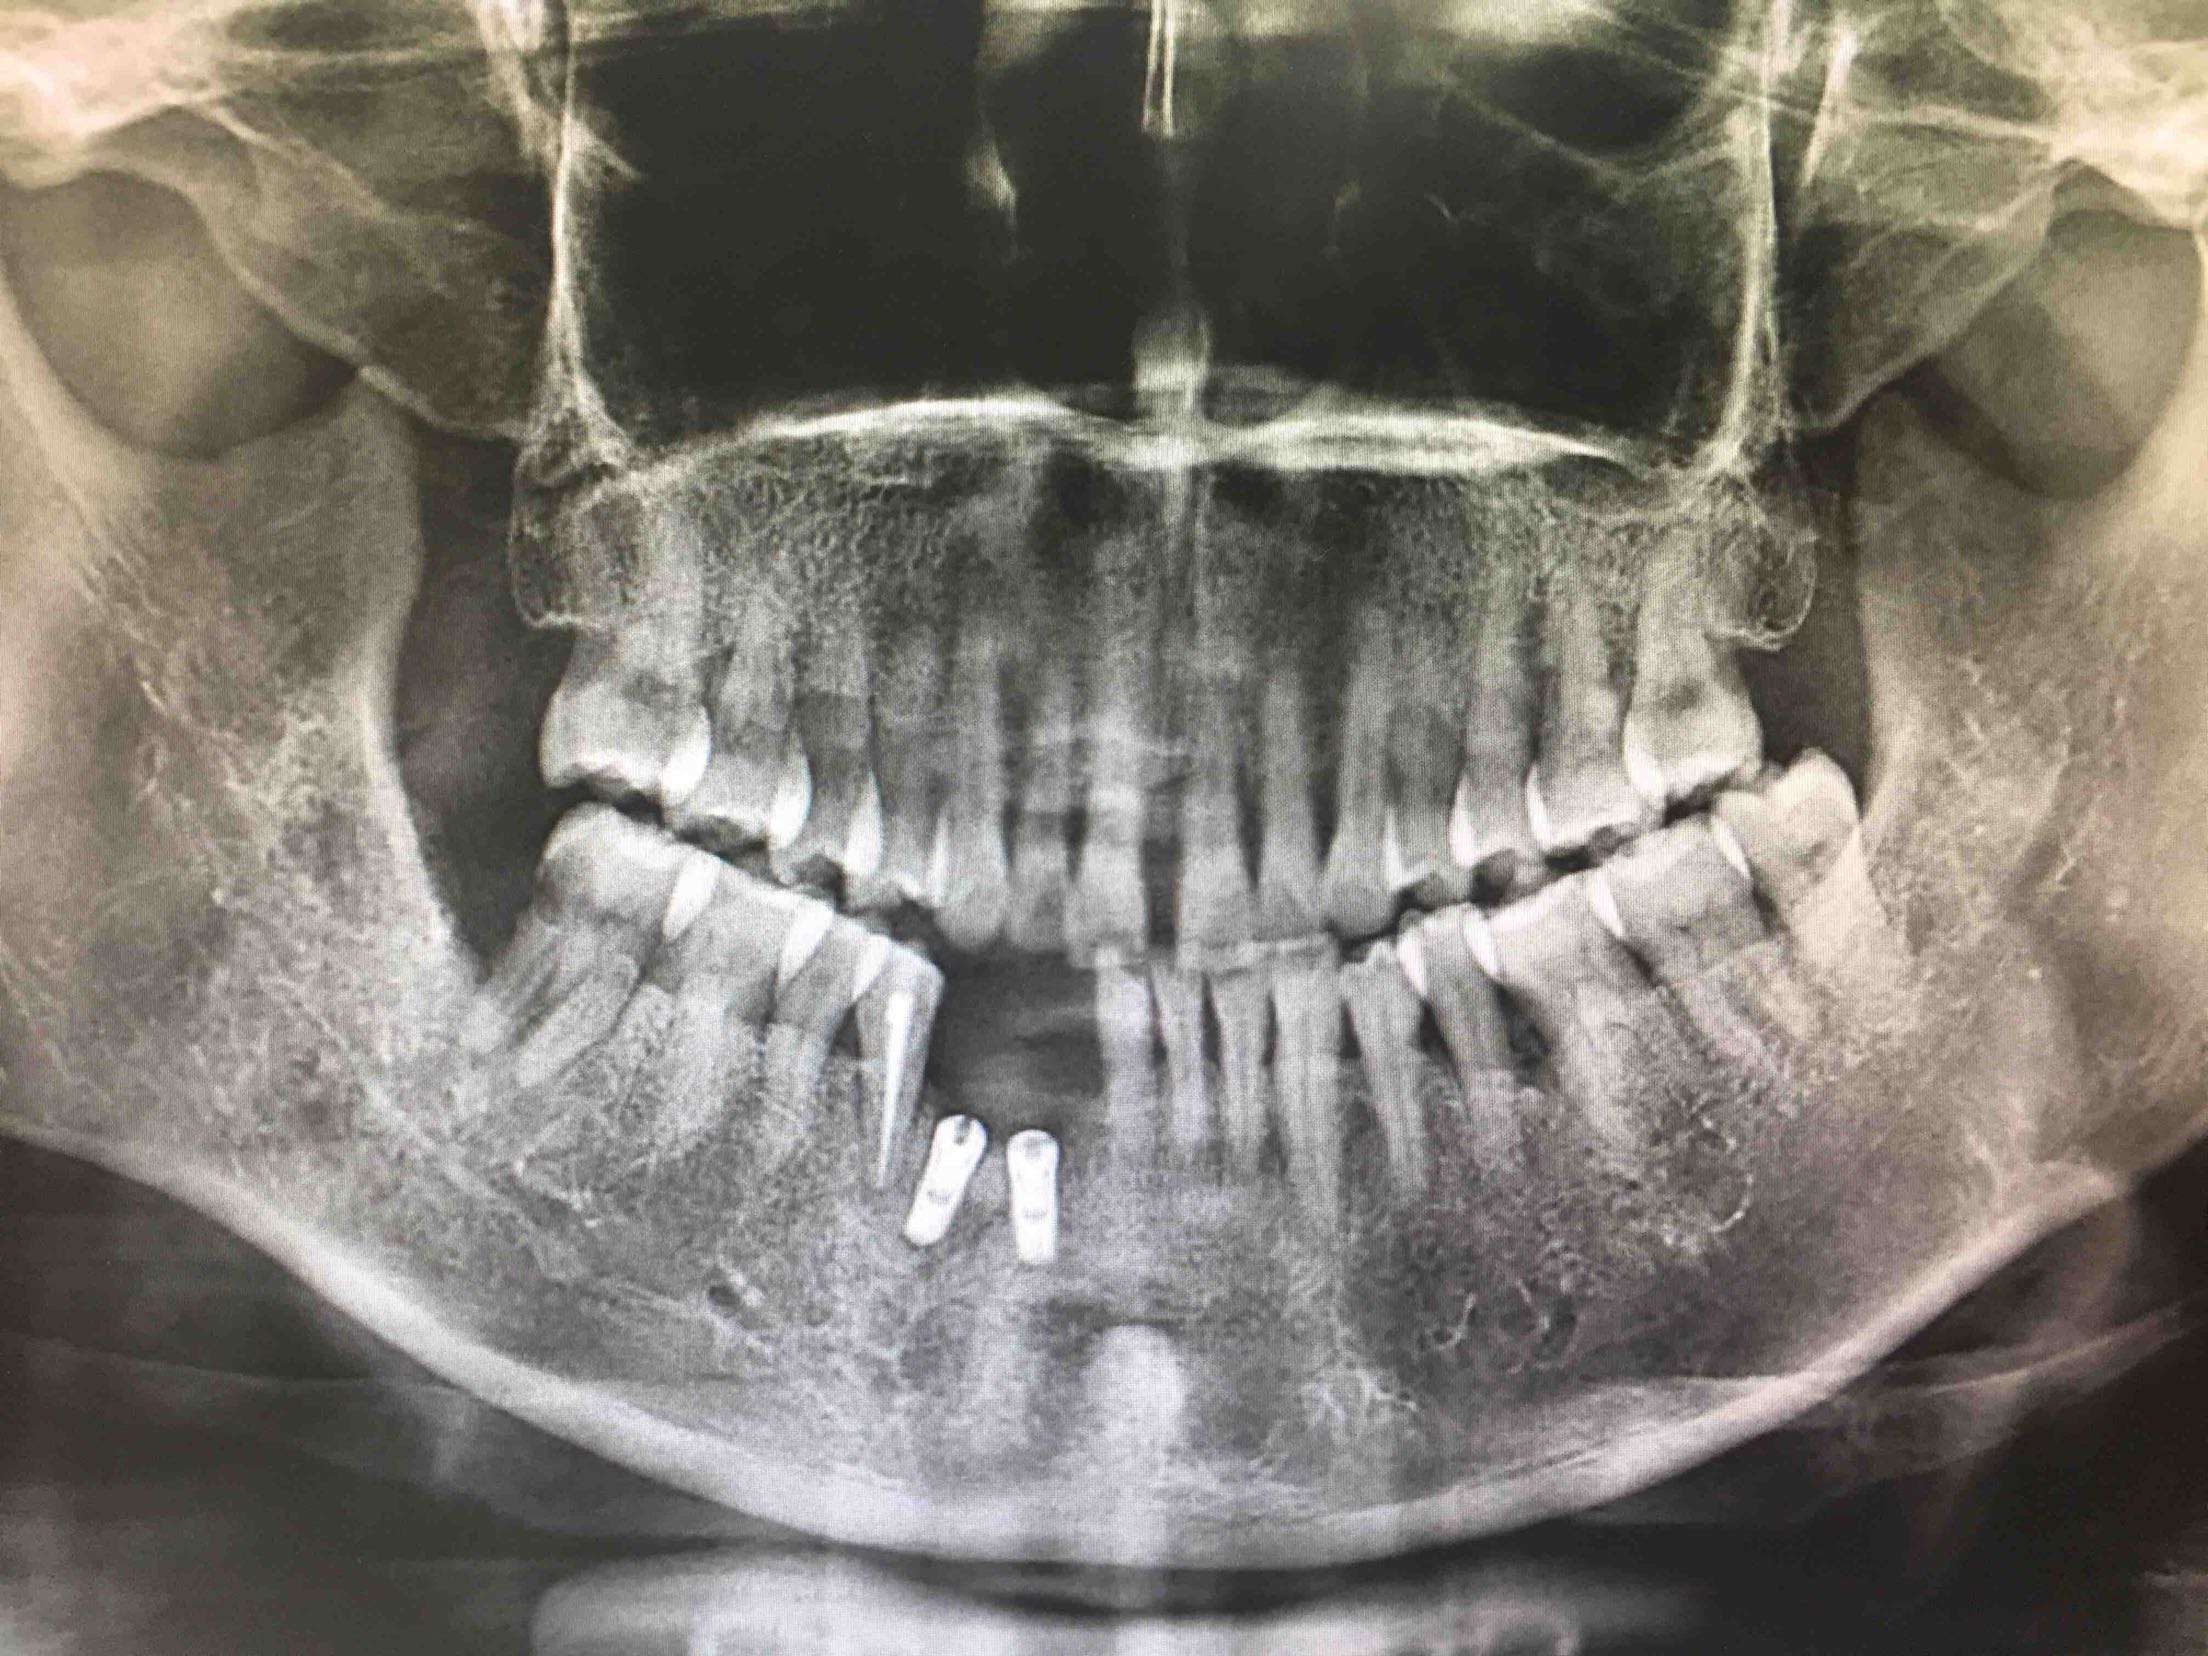

41、43、44牙松动2-3度,42牙缺失,全景片及CBCT显示牙槽骨吸收严重。

拔除41、43牙

两周后,局麻下,翻瓣拔除44牙,在41、42根方环形钻取骨块,钛钉固定于43牙骨缺损处,Bio-ss骨粉0.25g,海奥生物膜,严密缝合!嘱半年后植牙!

植入42、44登腾3.4-10两枚植体